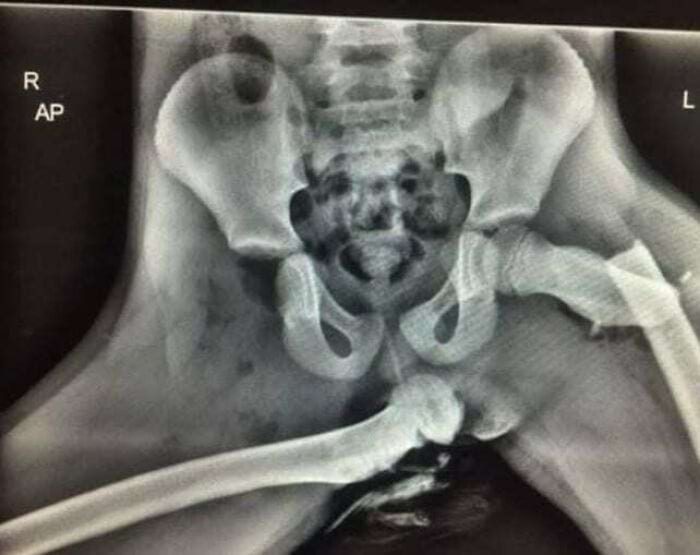

Рентгеновский снимок показывает, почему не стоит класть ноги на приборную панель автомобиля